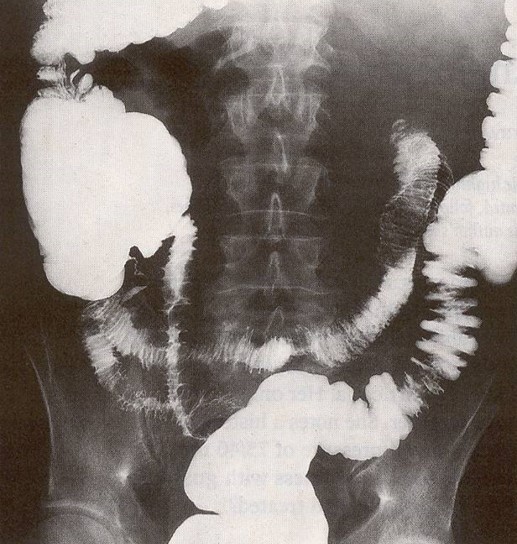

You are provided with an x-ray of her abdomen taken after the ingestion of gastrograffin and a picture of her hands (see below).

HEA is due to deficient levels of C1-inhibitor (C1INH) as a result of inherited or acquired mutations in the Serping-1 gene. Often in the setting of vascular trauma, such as might occur during a surgical or dental procedure, C1INH deficiency causes acute episodes of angioedema intitiated by activation of the classical pathway of complement and by binding of bradykinin to endothelial cell B2 receptors. The former reduces blood levels of complement components C1 and C4, the latter leads to activation of prekallekrein and factor XII → kallekrein and factor X!Ia → angioedema. As demonstrated in the present case, the angioedema can involve the gastrointestinal tract and present with acute onset abdominal pain and x-ray evidence of mucosal edema. The clinical clue to the diagnosis in the presented case is the concurrent edema of the hands. Angioedema caused by ACE inhibitors is also due to activation of the kallekrein system.